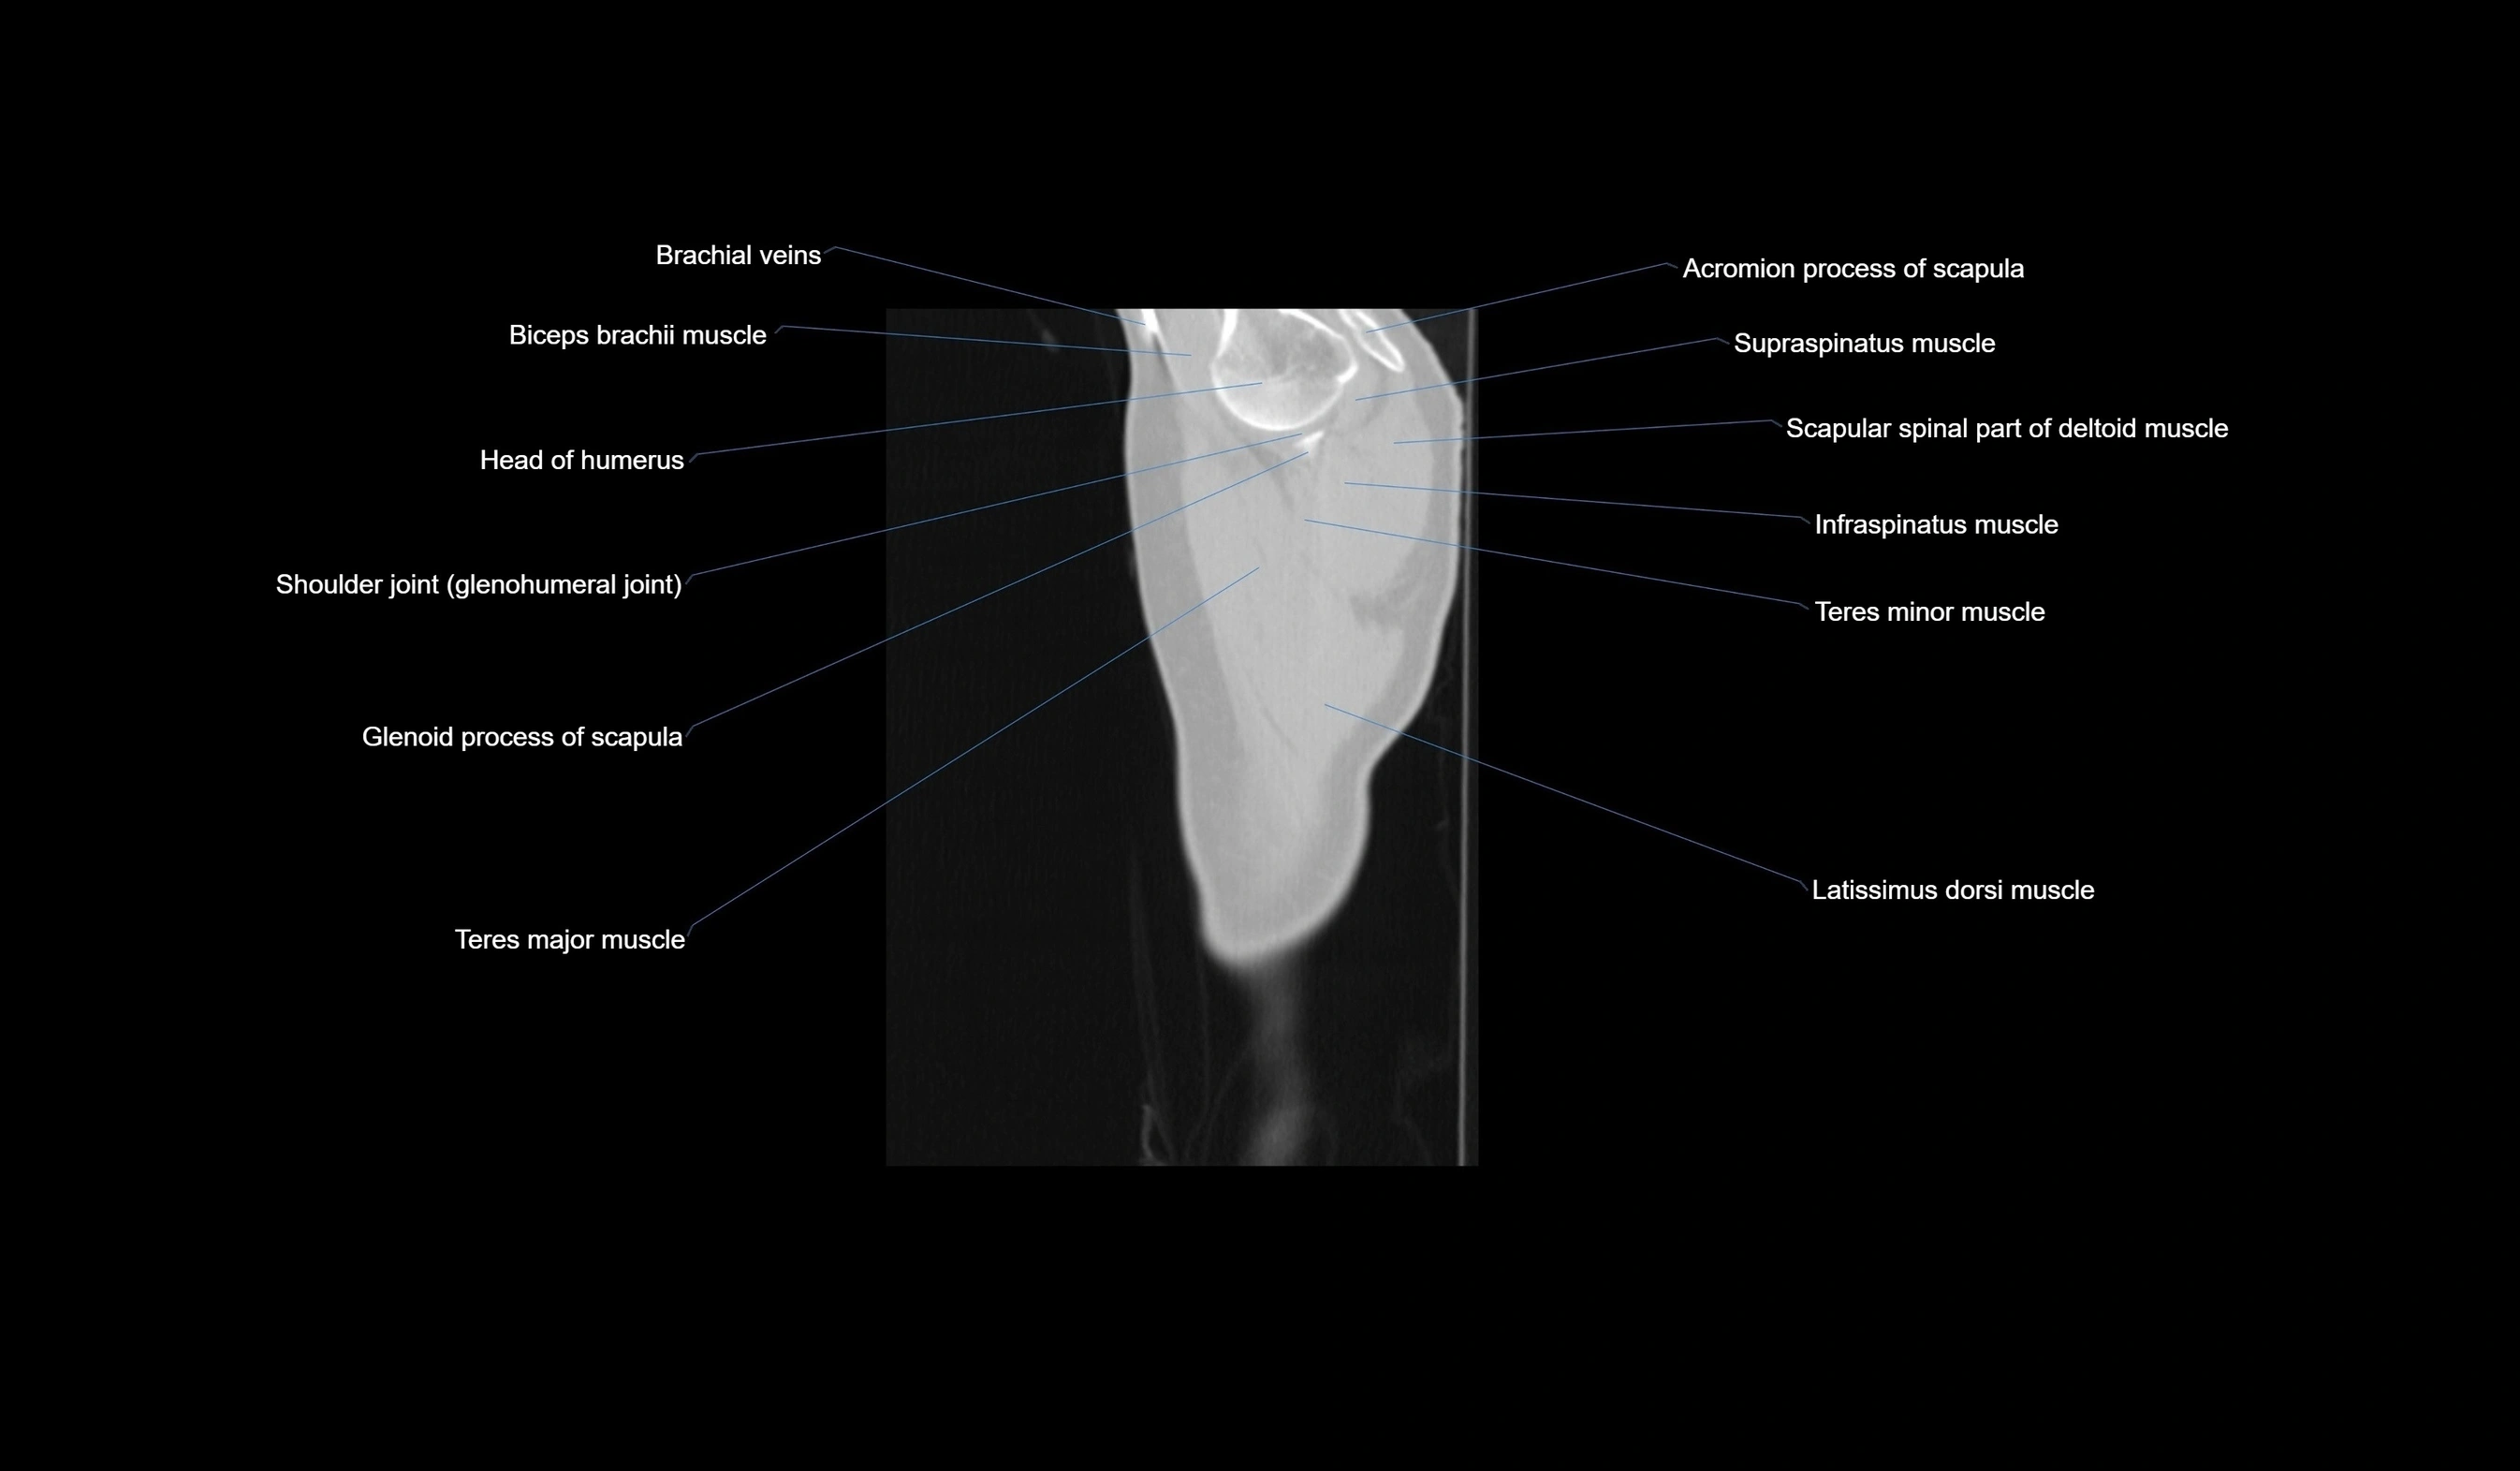

- Acromion process of scapula

- Biceps brachii muscle

- Brachial veins

- Glenoid process of scapula

- Head of humerus

- Infraspinatus muscle

- Latissimus dorsi muscle

- Scapular spinal part of deltoid muscle

- Shoulder joint (glenohumeral joint)

- Supraspinatus muscle

- Teres major muscle

- Teres minor muscle